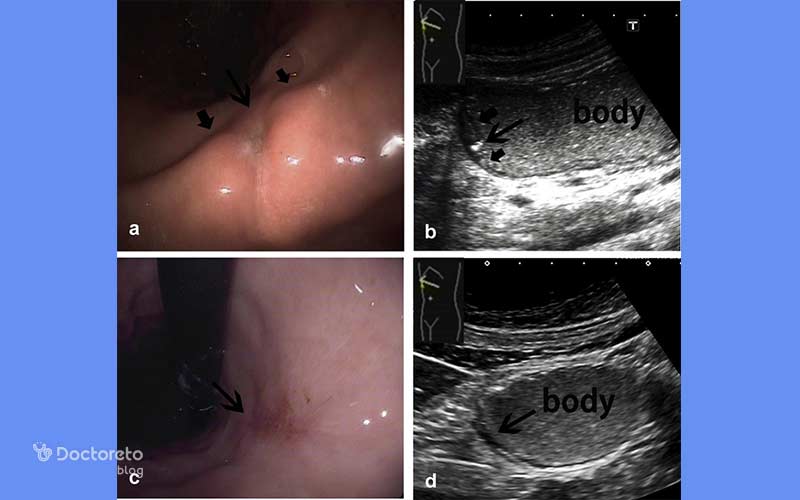

عکس تصویربرداری های سرطان معده خوش خیم

تصویربرداری پزشکی مانند سیتیاسکن و MRI به پزشکان کمک میکنند تا موقعیت، اندازه و ماهیت تومورهای معده را بررسی کنند. در ث تومورهای خوشخیم نیز این روشها کاربرد دارند تا احتمال نفوذ به بافتهای مجاور یا تبدیل احتمالی به بدخیم بیشتر و با دقت بالاتر ارزیابی شود. عکس این بخش نمونهای از این نوع تصویربرداریها را نشان میدهد.